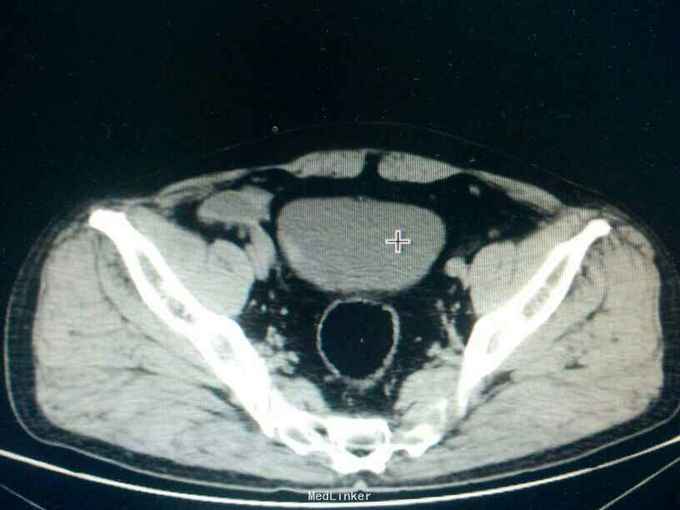

主诉:反复肉眼血尿3年。 病史:入院3年前,无明显诱因偶然发现小便呈淡红色,无明显尿频,尿急,尿痛,腰部疼痛发热等症状,后血尿广症状自行消失。一周前小便呈红色,为进一步检一治疗,来院检查。

专科查体无特殊。 ct检查结果提示,膀胱壁查见多个稍强回声闭,最大约3*3cm

诊断:膀胱癌。 治疗:膀胱肿瘤电切术,术后使用吡柔比星膀胱灌注。